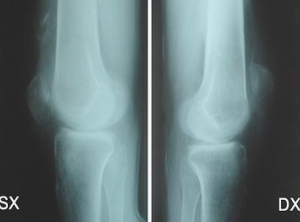

Les mesures non médicamenteuses et médicamenteuses sont discutées. L'accent est mis sur la bonne balance bénéfices-risques des interventions non-médicamenteuses et du paracétamol, et sur les risques liés aux AINS.